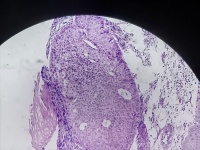

食管活检

男

61岁

食管癌

食管距门齿20cm处可见不规则病灶,质脆,易出血,管腔狭窄,镜子不能通过

食管粘膜活检

灰白色组织3块

考虑符合:鳞癌